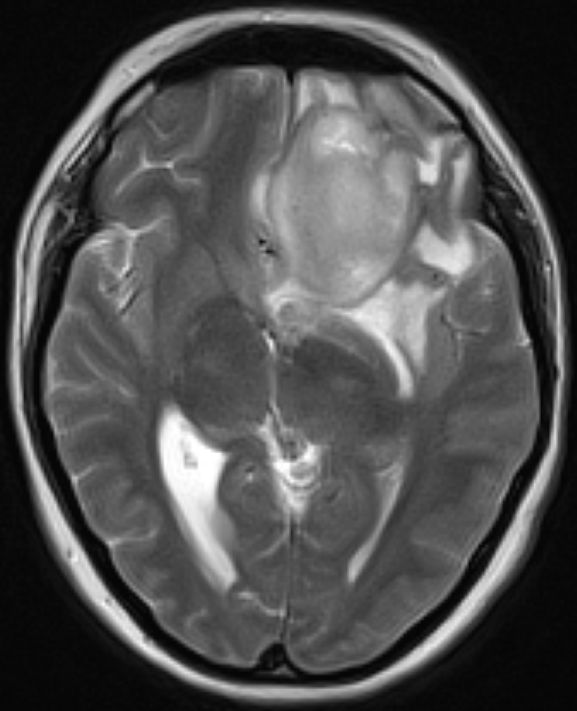

Zystisches Gliom parieto-occipital |

![]() |

![]() | ||